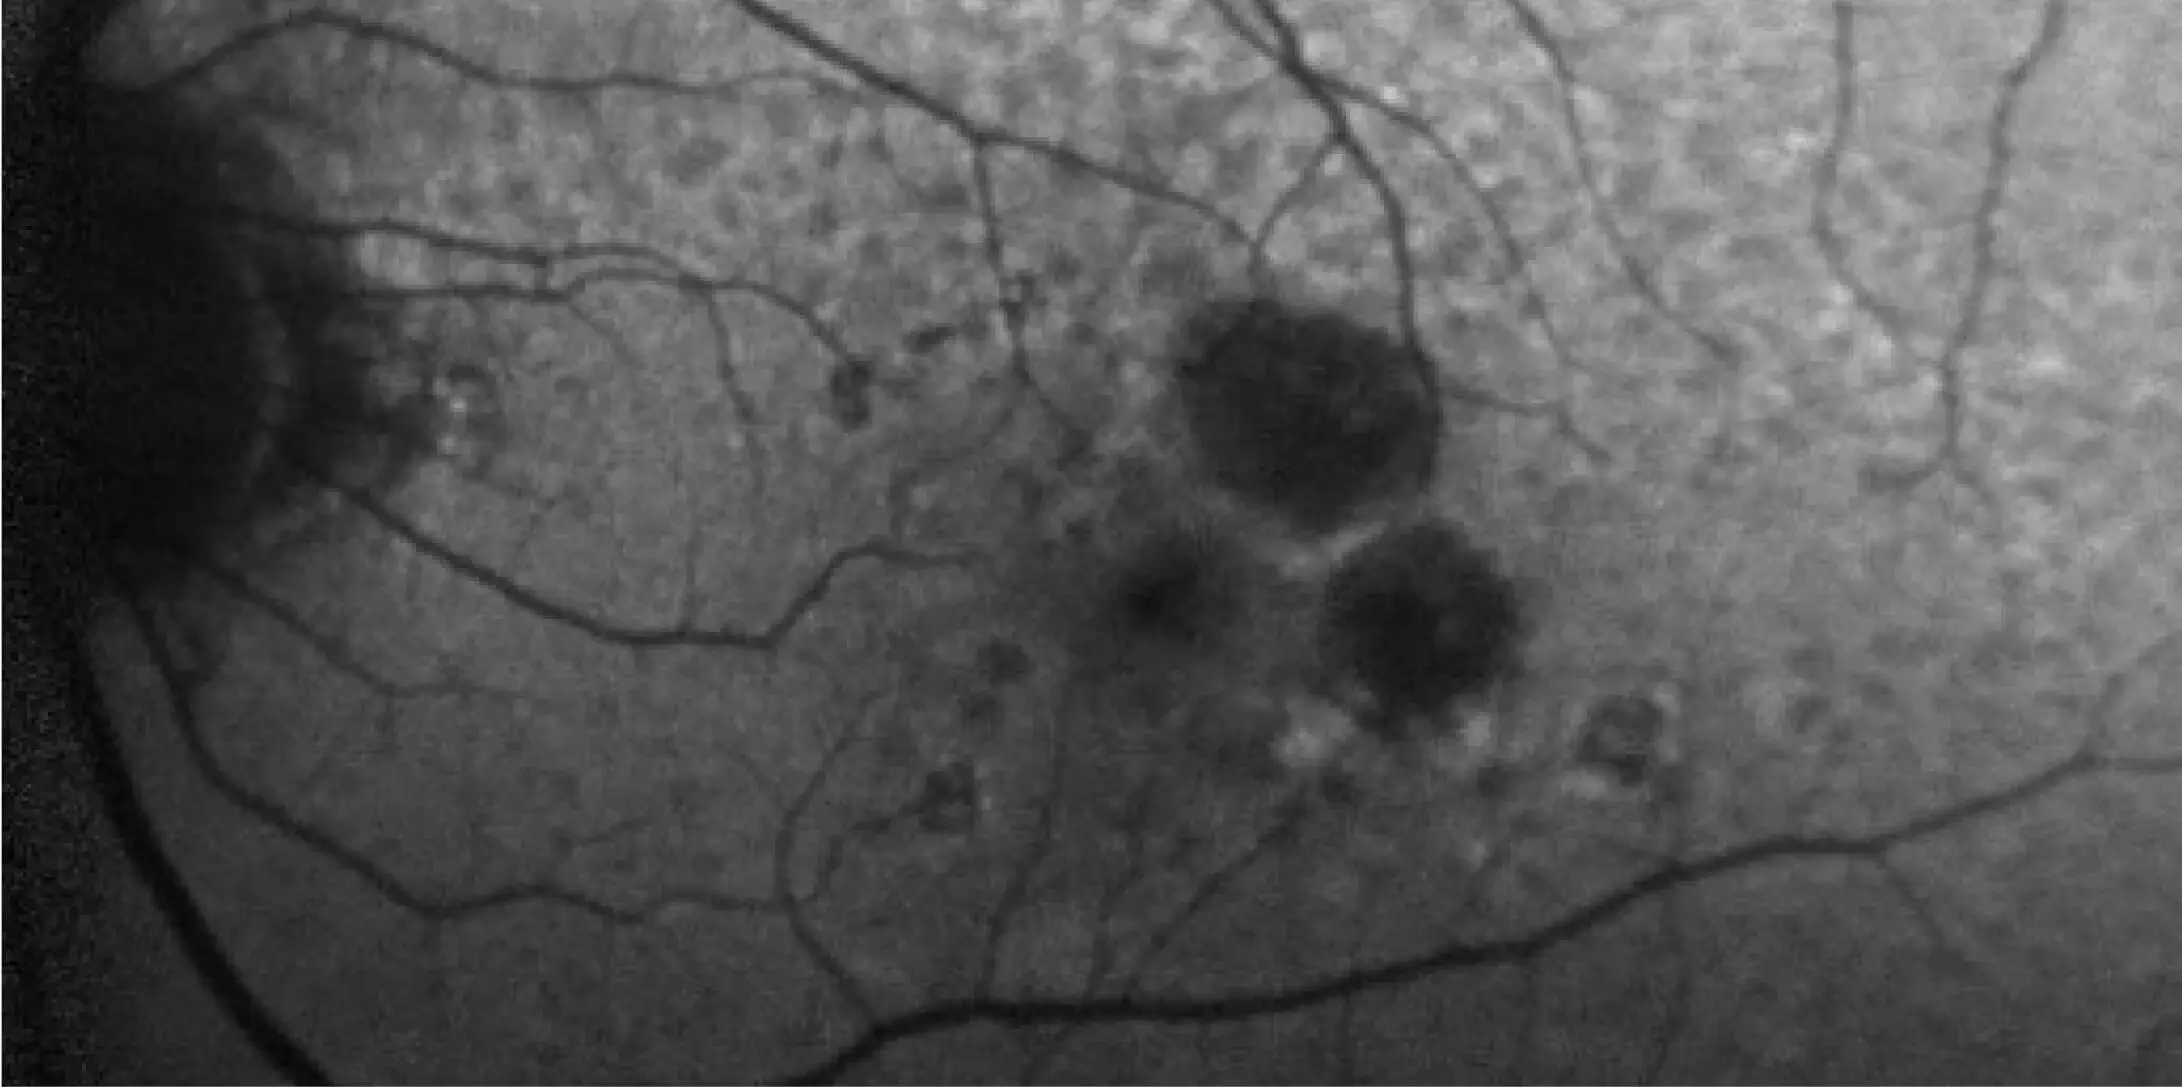

Fundus Autofluorescence (FAF)

Image courtesy of Dr. Mark Dunbar.

FAFUseful for visualizing progression and educating patients2,3,9

Dark hypofluorescence indicates areas of atrophic lesions, whereas lighter hyperfluorescent areas highlight accumulation of lipofuscin, which is prognostic of GA progression.2